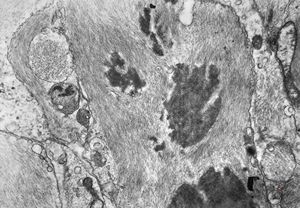

M,10y. | herpetic encephalitis